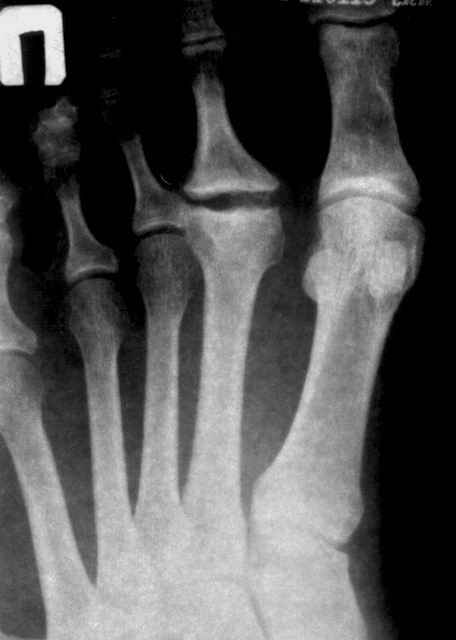

Уважаемые коллеги. Обратился мужчина 58 лет с жалобами на боли в области 2 пальца стопы. Болел ли раньше палец, добиться не удалось, но вспомнил, что лет 10 назад ударился стопой, "вывихнул 2 палец". Боли постепенно уменьшились. А несколько месяцев назад стали беспокоить боли, особенно при ходьбе. Около месяца назад получил еще травму- упал радиатор, но как выяснилось больше придавило, чем ударило. Сейчас ходит опираясь только на пятку, проблемы с обувью, пальпация болезненна в области головки 2 плюсневой кости.Пассивные движения ограничены незначительно, активные - тыльное сгибание градусов 10.Мнения разошлись насчет диагноза: деформация головки - это КелерII? Чем можно помочь пациенту? Если подлежит оперативному лечению, то какие возможные варианты реконструкции стопы? С уважением А. Минервин.

У меня была похожая пациентка - тоже с вальгусной деформацией, неуточненная травма 3 года назад. Обратилась по поводу болей в области головки 2 плюсневой кости, в течение 2-х месяцев. При осмотре - небольшая припухлость, движения в суставе в полном объеме, даже некоторая "разболтанность" отмечается. Боли усиливались в основном при ходьбе на каблуке, когда увеличивалась нагрузка на головку плюсневой кости. У неё были более выраженные изменения на Rg-грамме (во вложении), а здесь - только если в прямой проекции (справа) можно заподозрить некоторую уплощенность головки...

Налицо анамнестически, визуально и рентгенологически остеохондропатия головки II пл. кости (Келер II). В отношениии I пФс - предполагаю деформирующий артрозо-артрит как этап формирования hallux regidus. Консервативное лечение, как предложил Игорь Кучерявый, возможно использование Дипроспан интра- и параартикулярно в период обострений. Оперативно I пфс: 1 при выраженных изменениях в суставе и стойком болевом синдроме - артродез, с использованием винтов, положение пальца строго 5 гр. тыльной флексии; 2 - эндопротезирование. На II пфс мы используем два вида оперативного лечения: 1 - артропластика с частичной резекцией патологически измененной головки и её последующим остеосинтезом; 2- эндопротезирование протезом из корундовой керамики (см. Вестник травматологии им.Н.Н.Приорова №3, 2005).

Уважаемые коллеги, асептический некроз головки 2 плюсневой кости - болезнь Фрайберга. По сути, чтобы избавиться от болей в данном суставе, хватает резекции головки. Консервативно - дипроспан. Хотя принимая во внимание вальгусную деформацию 1 пальца и молоткообразную деформацию 2 пальца, предпочтительно все же предложить пациенту реконструкцию переднего отдела стопы. Судя по снимку, латеральная сесамовидная кость полностью вывихнута в 1 межпальцевый промежуток - следовательно, нужна остеотомия 1 плюсневой кости. Шеврон или скарф. 2 палец - резекция головки 2 плюсневой кости + Гоман.

если бы речь шла о чистой остеохондропатии, то мне мысли Юлии Олеговны казались бы ближе всех к истине, но давайте обратим внимание на боковую проекцию: кто-нибудь видит какие-либо изменения, кроме углового смещения головки в подошвенную сторону?

Мне картина видится такой: жил себе пациент с молоткообразным ІІ пальцем, что характерно при такой вариации в длине I и II плюсневых костей, это и вызывало боли в ступне. Месяц назад "придавил" II пфс радиатором, получил перелом головки ІІ пястной кости с подошвенно-угловым смещением (приложение силы основной фаланги ІІ пальца), сейчас перелом почти сросся (линия перелома еще слегка прослеживается).